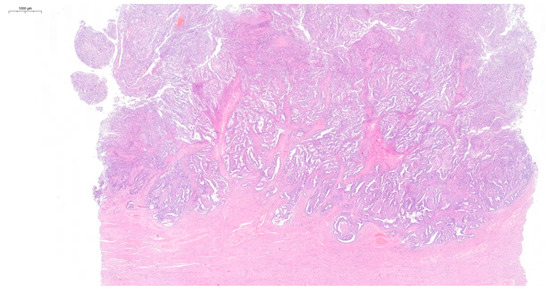

On the day of admission, the female was in good general condition. A gynecological examination demonstrated a normal-sized, retroverted body of the uterus, displaced to the right, with limited mobility. A tumor approximately 10 cm in diameter, with limited mobility, was detected behind the uterus on the left side. The ultrasound findings were as follows: the body of the uterus was homogeneous, measuring 45 × 57 mm; the endometrium was 6.3 mm thick and a small amount of free fluid behind the uterus was detected (Figure 1a); the right ovary measured 29 × 23 mm (Figure 1b); and the left ovary appeared as a solid-cystic tumor of 91 × 73 mm (Figure 1c). A multiple vascular pattern in the Doppler ultrasound was confirmed. The blood tests revealed a cancer antigen 125 (CA 125) level of 437 mIU/mL, a human epididymis protein 4 (HE-4) level of 481 pmol/L, and a Risk of Ovarian Malignancy Algorithm (ROMA) score of 95.6%. The patient qualified for surgical treatment.

Figure 1.

Ultrasound on the day of admission.